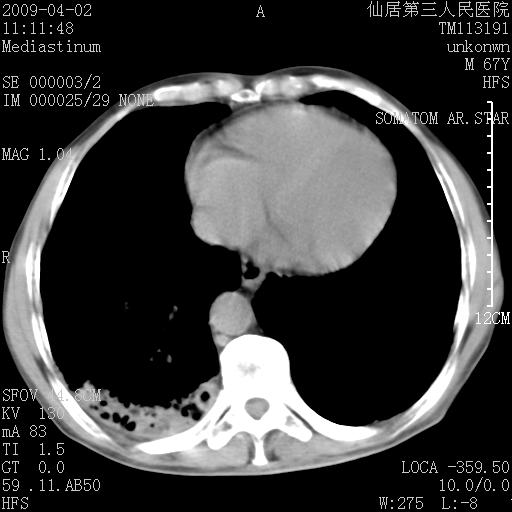

患者老年男性,乏力畏寒来诊,摄胸片示右下肺感染性病变,抗炎两周后复查胸片,无好转有进展。

后做ct平扫表现如下:

病灶呈蜂窝征,纵隔多个淋巴结肿大;肺泡癌需考虑

我认为普通的感染应该可以除外,间质性肺炎可能性较大,但如何解释纵膈的淋巴结肿大呢